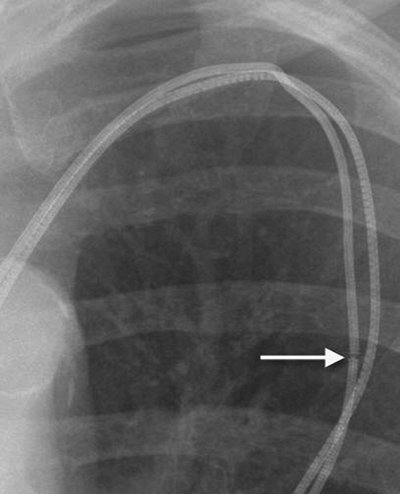

The pulmonary artery catheter balloon appears radiographically as a 1-cm rounded radiolucency at the tip of the catheter (Fig. 5-9). The balloon should be inflated for only a very short period of time, during measurement of pressure, and it should not be inflated while chest radiography is performed. If the balloon is left inflated, it can obstruct a major pulmonary artery and lead to pulmonary infarction.

FIGURE 5-9. Inflated pulmonary artery catheter balloon. AP recumbent intraoperative chest radiograph, taken during measurement of pulmonary capillary wedge pressure, shows the inflated radiolucent balloon at the tip of the catheter (arrows). Normally, the balloon should not be inflated during the time of radiographic exposure. The balloon should be inflated for only a short period while measurements are obtained and then immediately deflated; when left inflated for longer periods, blood flow distal to the balloon is interrupted, resulting in pulmonary infarction.